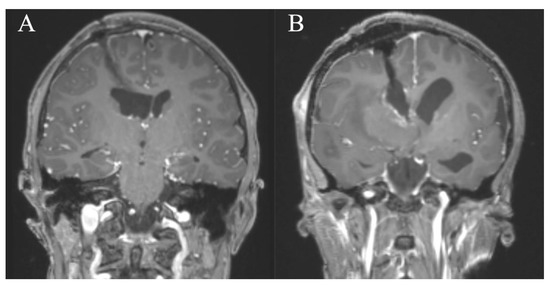

In all patients, a GTR/NTR could be achieved (Table 3). The pre- and postoperative scans of cases no. 3, 6, and 7, which were all treated through an EA approach and case no. 8, which was treated through a PE approach, are shown in Figure 3, Figure 4, Figure 5 and Figure 6. In one patient (case no. 5), due to her advanced age, we referred from resecting the vascularized capsule of the colloid cyst, achieving NTR. The mean surgery time was 163.6 ± 54.2 min (range 82–240 min) and the average blood loss was 142.5 ± 90.4 mL (range 50–300 mL). The PE approach was associated with lower mean blood loss than the EA approach (87.5 ± 47.8 mL vs. 197.5 ± 93.2 mL, p = 0.114). In four patients (50%), a total of six postoperative complications occurred, of which all were transient. Two patients (25%) showed transient cognitive impairments after resection of a colloid cyst, most likely directly associated with the endoscopic approach. The remaining four transient complications were unrelated to the use of endoscopy or NUA (Table 3). The two patients with neuropsychological evaluation showed postoperatively scores of 18/30 and 25/30 points, respectively, with a documented improvement in both patients at follow-up (18/30 to 24/30 points within 35 days and 25/30 to 30/30 points within 114 days). With regards to the remaining adult patients, no evaluation was carried out, because there was no evidence of neurocognitive deficits subjectively. In the two children with intraventricular lesions, no postoperative neurocognitive assessment was performed (due to autism disorder in the context of tuberous sclerosis in one case and due to the very young age of 5 months in the other case) (Table 3). At follow-up (15.9 ± 6.3 months; range 6.8 to 23.2 months), all patients showed improved or unchanged mRS when compared to the mRS at discharge. Complete regression or improvement of the preoperative complaints was seen in all patients, while MRI at follow-up showed no recurrence in any of the cases (Table 3).

Figure 3. Case 3. Axial and sagittal MR images, T1-weighted sequences with contrast medium preoperatively (A,B) and immediately postoperatively (C,D) after resection of the intraventricular meningeoma via a right parietal endoscopic-assisted approach.